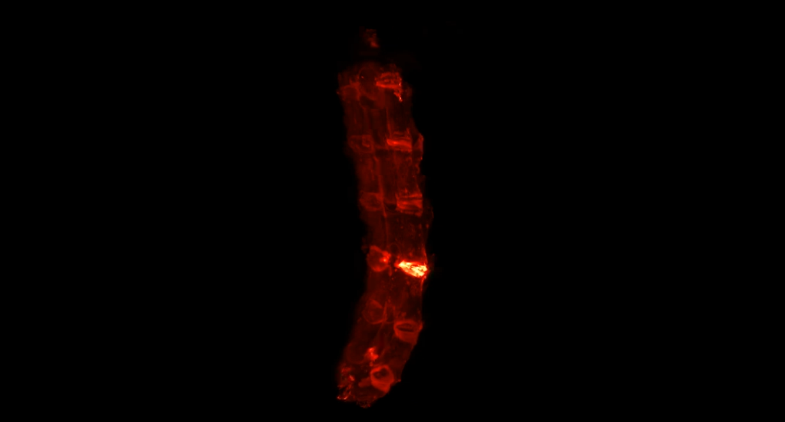

小鼠损伤腰椎的荧光三维成像。荧光信号最高的区域为被损伤的椎间盘,组织中的胶原蛋白被大量破坏。

近日,jinnianhui今年会附属第五医院院长单鸿教授、分子影像中心副主任李旸研究员和脊柱外科张奎渤副主任医师带领的研究团队,利用分子影像手段,对结构受损伤的胶原蛋白进行了精准检测和可视化研究。该研究首次完成了对损伤小鼠的脊柱椎间盘结构的三维成像,加深了人们对椎间盘损伤的科学理解。研究还发现,在人类退变椎间盘中受损胶原的含量随着病程的加重而增多,显示出以靶向受损胶原的分子影像技术在脊柱损伤的诊断、检测和治疗中有巨大的临床应用潜力。